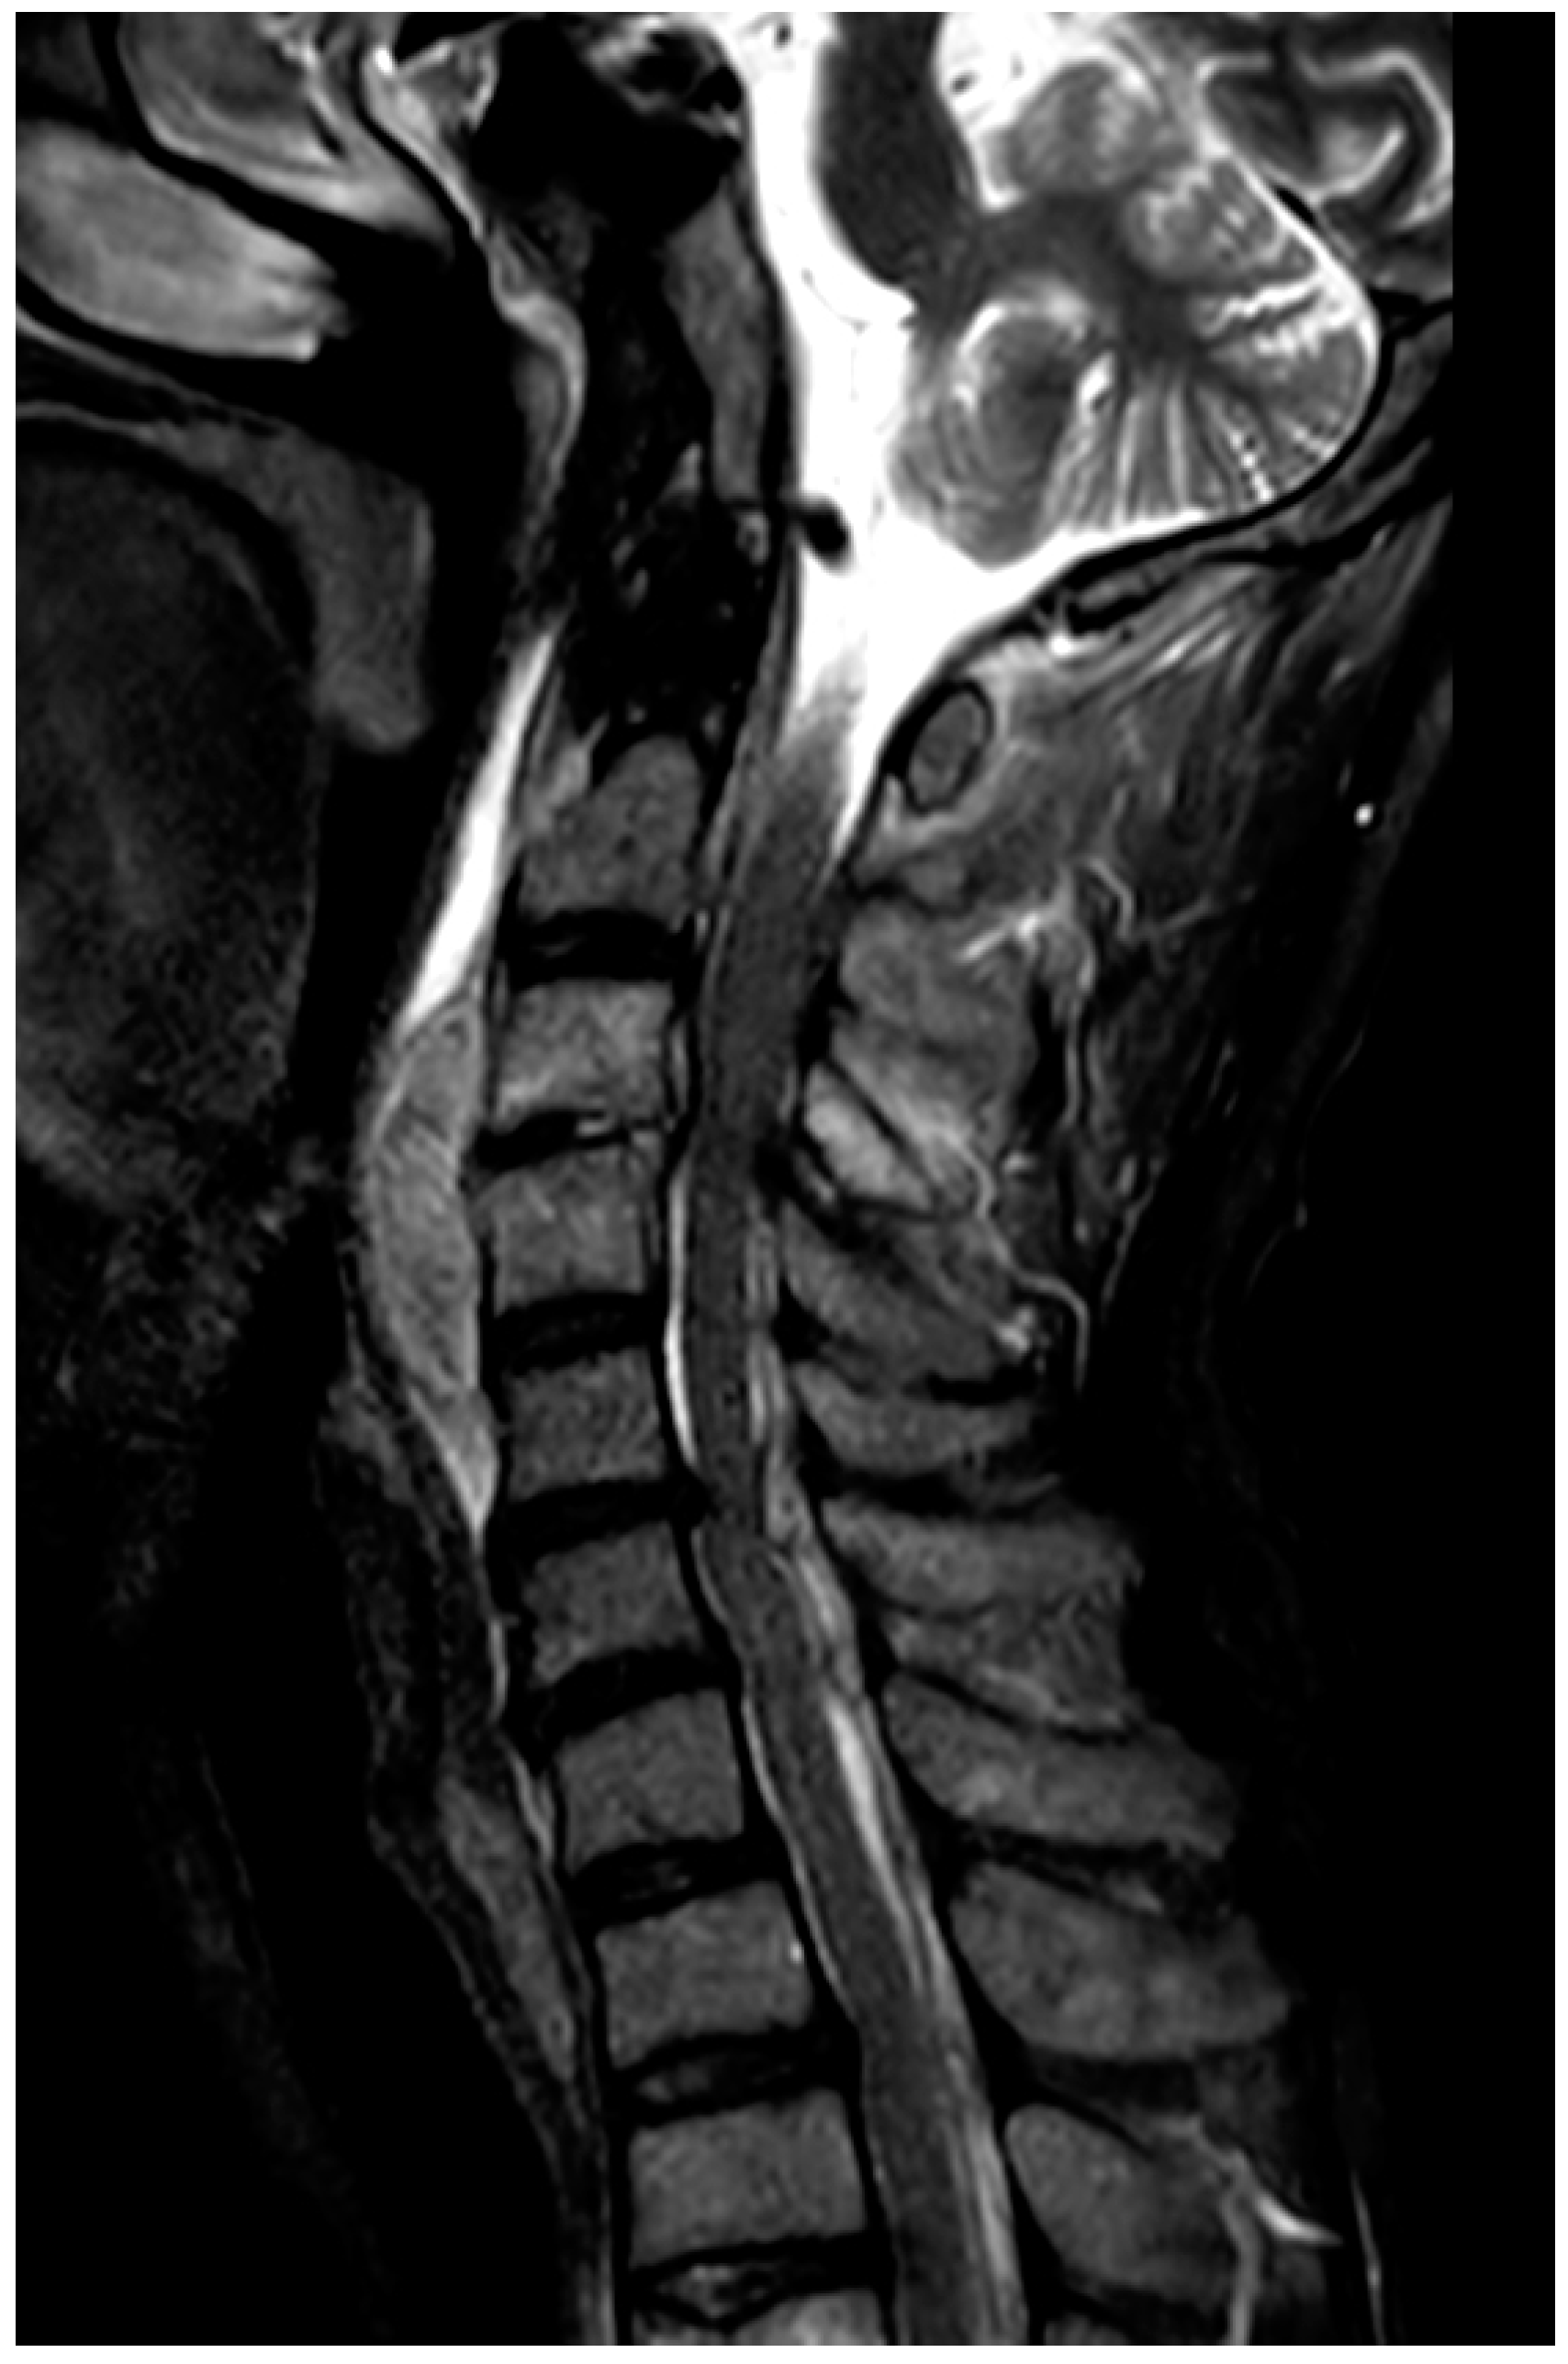

Cervical Epidural Abscess Secondary to a Post-Traumatic Hematoma, Successfully Treated with Adjunctive Hyperbaric Oxygen Therapy: A Case Report

2. Case Presentation